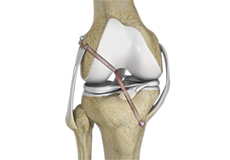

Multiligament Reconstruction of the Knee

Multiligament knee reconstruction is a surgical procedure to repair or replace two or more damaged ligaments of the knee joint. The surgery can be performed using minimally invasive techniques.